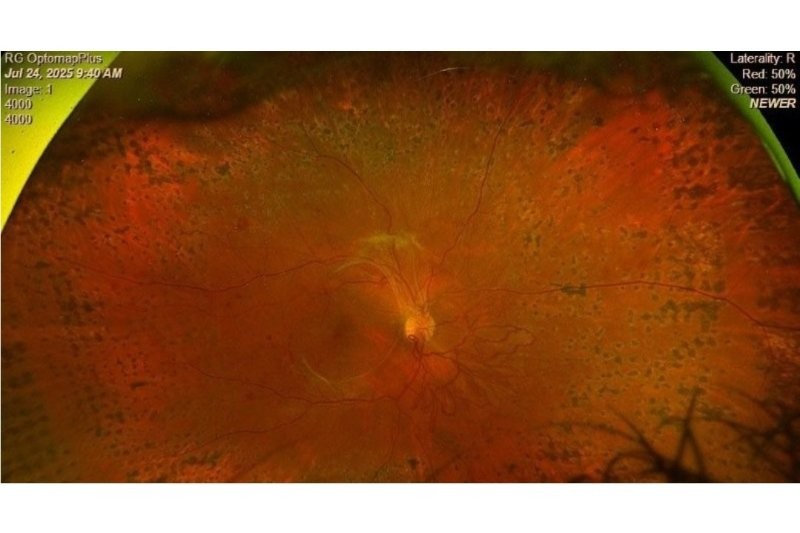

Paediatric ophthalmology research review February 2026

Dr Julia Escardό-Paton 01/02/2026